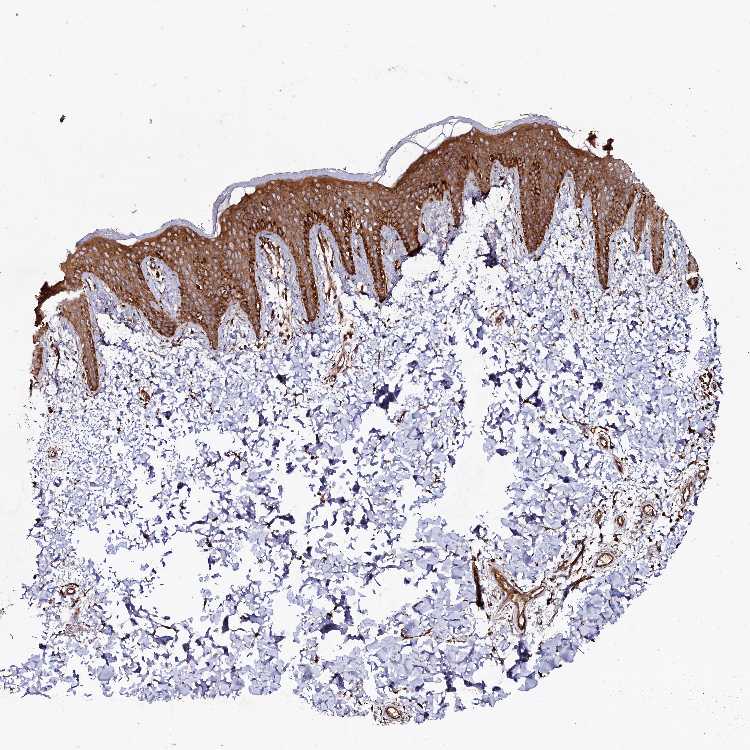

SKIN 1 - Antibody stainingi

Antibody staining in the annotated cell types in the current human tissue is reported as not detected, low, medium, or high, based on conventional immunohistochemistry profiling in selected tissues. This score is based on the combination of the staining intensity and fraction of stained cells.

Each image is clickable and will lead to virtual microscopy that enables deeper exploration of all samples and also displays staining intensity scores, fraction scores and subcellular localization as well as patient and tissue information for each sample.

Antibody HPA039357

Langerhans Medium

Fibroblasts Medium

Keratinocytes High

Melanocytes High

SKIN 2 - Antibody stainingi

Epidermal cells High